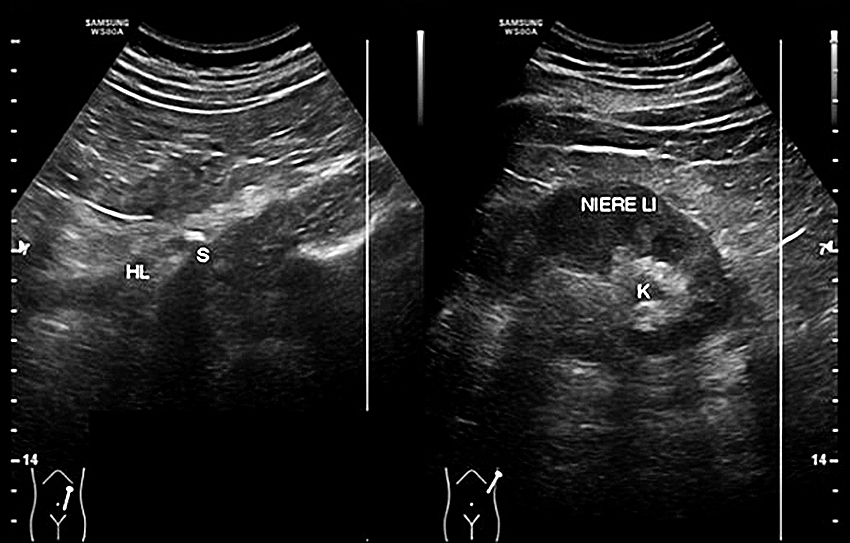

Durch ein low-dose- oder Nativ-CT vom Abdomen können neben den Kelchsteinen die Harnleitersteine sehr sicher nachgewiesen oder ausgeschlossen werden. Durch die immer besser werdenden Sonographiegeräte lassen sich allerdings auch bei geringen Aufweitungen die Ursachen der Obstruktionsstörung des oberen Harntraktes finden. Die Kindernephrologen und Kinderradiologen versuchen schon seit längerem, auf radiologische Diagnostik am oberen Harntrakt zu verzichten, da hier die Strahlenbelastung noch mehr Bedeutung hat. Auch für die Erwachsenenurologie sollte die Reduzierung der Strahlenbelastung bei der Abklärung der Harnstauungsniere ein Argument sein.

Bei den distal-prävesikalen Steinen hat der transrektale Ultraschall schon längere Zeit seine Bedeutung gefunden, allerdings nur bei wenigen Untersuchern. Bei Frauen eignet sich dazu der transvaginale Schall, der den Harnleiter bis zur Gefäßkreuzung verfolgen und den erweiterten Harnleiter komplett mit dem transabdominalen Schall auf eine Steinobstruktion untersuchen lässt. In der gynäkologischen Abteilung steht mir seit 2/2017 ein high-end-Sonogerät der Fa. Samsung WS80A zur Verfügung.

Bei den 295 stationären Patienten mit Nierenkoliken hatten 111 Patienten einen proximalen Stein, bei 184 Patienten wurde der Stein distal der Gefäßkreuzung gesichert. Bei den prävesikalen Steinen konnte in der transrektalen Sonographie der Stein bei den Männern in den letzten 3,5 cm sicher gesehen, in der vaginalen Sonographie der Harnleiter mit dem Stein teilweise bis zu den iliakalen Gefäßen verfolgt werden.

Bei den 111 Patienten mit proximalen Steinen konnten die Steine bei 102 Patienten (92 %) auch im Ultraschall gesehen werden. Bei 59 Patienten (53 %) war für die Steinsicherung kein CT angefordert worden. Bei den 184 Patienten mit distalen Harnleitersteinen wurde der Stein bei 171 Fällen (93 %) in der transrektalen/transvaginalen Sonographie verifiziert, bei 123 Patienten (66 %) wurde auf eine CT-US verzichtet. Fornixrupturen konnten bei den letzten 50 Patienten zu 22 % durch high-end-Geräte gesehen werden, immer ohne klinische Konsequenz; bei 6 Patienten wurde bei der Aufnahmeuntersuchung eine Urosepsis erkannt und durch die alleinige sonographische Steinsichtung rasch einer endoskopischen Steinsanierung zugeführt.